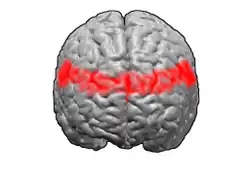

Image

-

Animation.

Animation. -

front view.

front view. -

Lateral view.

Lateral view. -

Medial view.

Medial view.